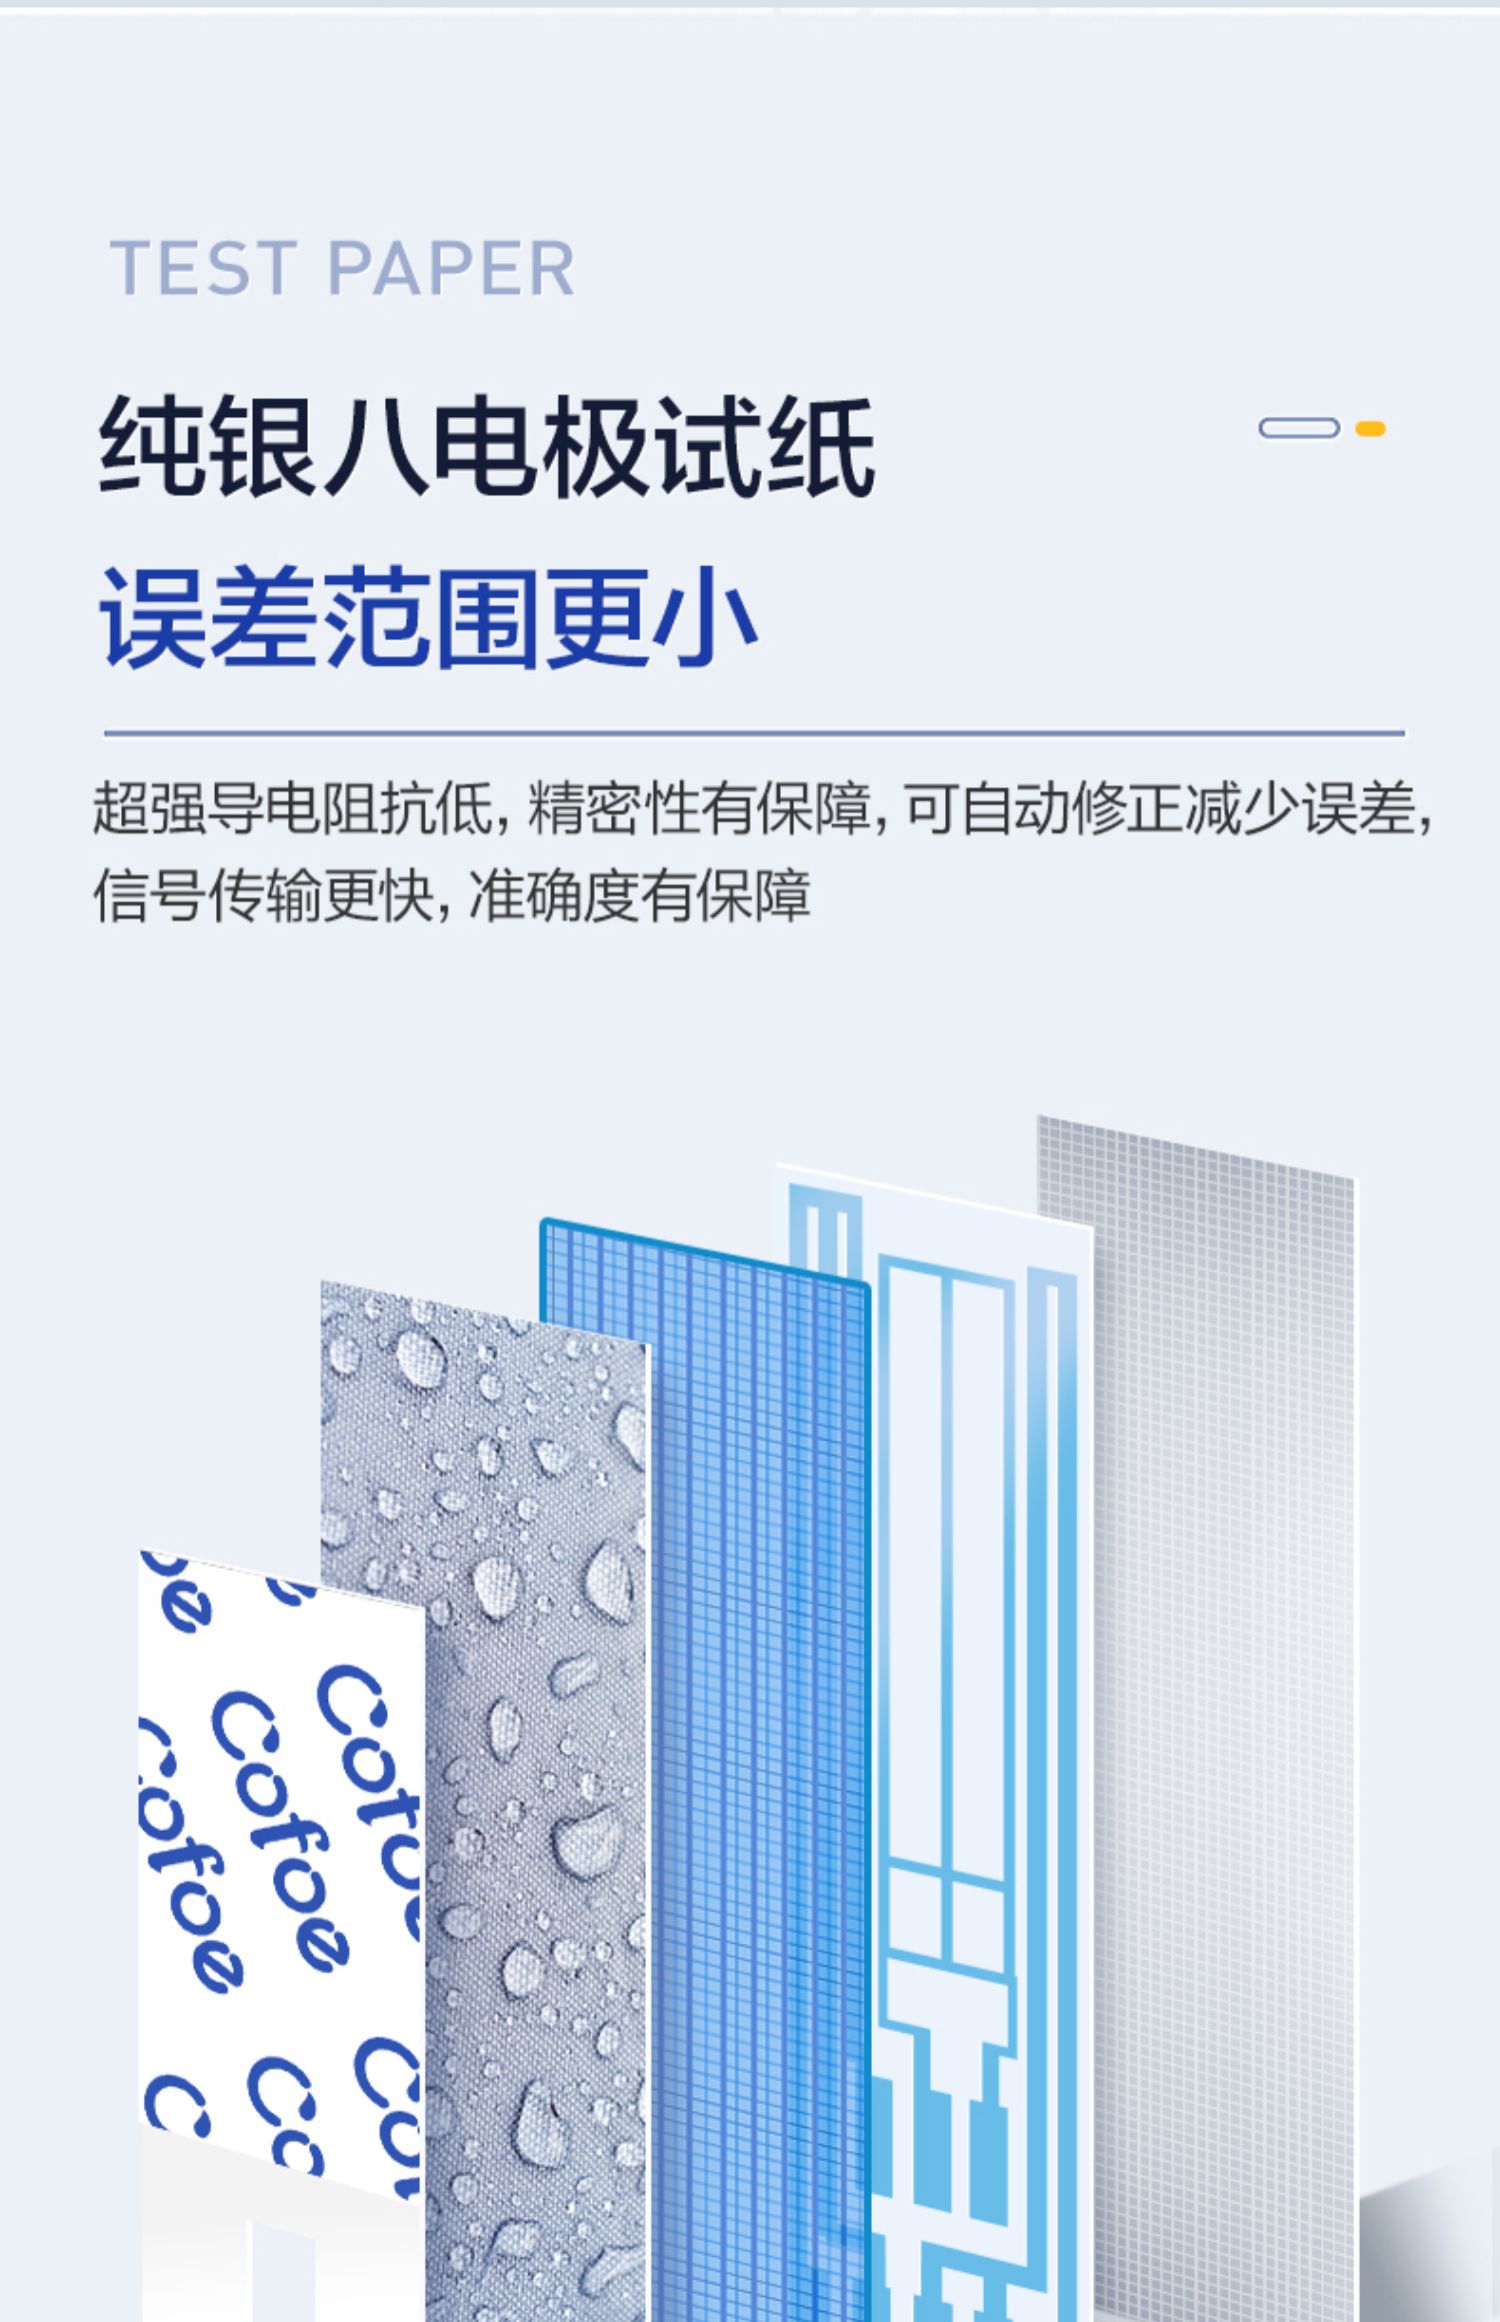

可孚新国标血糖测试仪家用测糖仪试纸官方旗舰店测血糖的仪器孕妇

Фото та опис товару